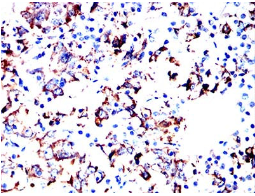

IHC    1/200 - 1/1000

Species Reactivity:    Human

Immunogen:    Purified recombinant fragment of human PRL (AA:29-227) expressed in E. Coli.